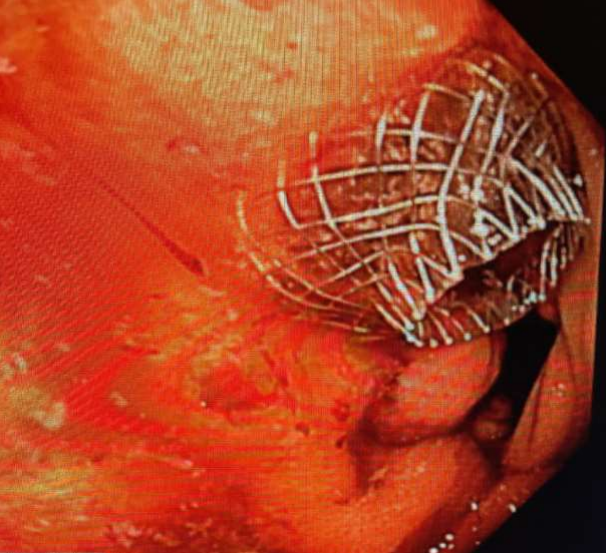

73 year-old gentleman presented with jaundice, nausea, and vomiting. The workup showed biliary obstruction and duodenal obstruction due to pancreatic adenocarcinoma. He was not a candidate for surgery due to metastatic disease. The endoscopic examination showed severe duodenal obstruction starting at the junction of first and second part of the duodenum. Since ampulla could not be accessed, ERCP was not possible. EUS (Endoscopic Ultrasound) guided choledochoduodenostomy (Fig. 1) was performed using electrocautery enhanced 8 mm x 8 mm lumen-apposing metal stent (LAMS) (Axios stent, Boston Scientific Corp, MA, USA) for biliary obstruction. In the same session duodenal obstruction was relieved by placing uncovered duodenal stent 22 mm x 12 cm, (Fig. 2) (Boston Scientific Corp, Marlborough, Mass, USA). The jaundice was completely relieved and due to the relief of duodenal obstruction by the duodenal stent he was able to tolerate low residue diet. He received chemotherapy. A year later his nausea and vomiting recurred. The endoscopic evaluation and upper gastrointestinal barium contrast study did confirm recurrent duodenal obstruction. We discussed various treatment options with the patient and he elected to have minimally invasive non-surgical EUS guided gastroenterostomy as opposed to surgical gastrojejunostomy.

Figure 1. Lumen-apposing metal stent (LAMS) Axios 8 mm x 8mm placed via EUS creating choledochoduodenostomy to overcome biliary obstruction

Figure 1